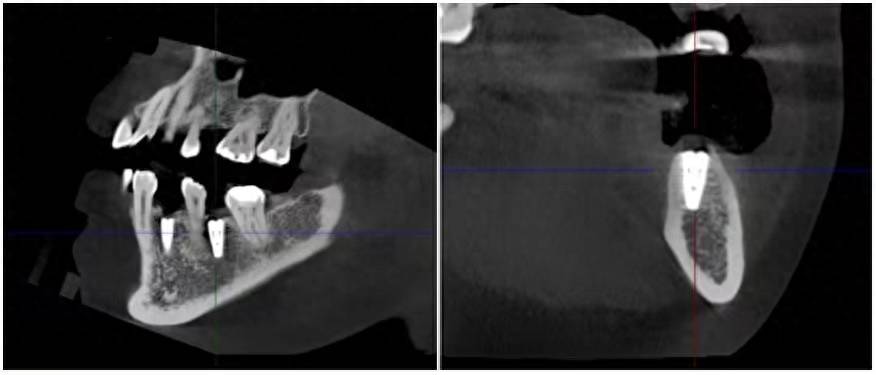

“与传统种植牙手术相比,机器人种植牙最大的优点就是精确。自主式口腔种植牙机器人将种植体的植入误差由手动操作的2㎜缩小到0.3㎜以内,本次手术中两位患者的术后CBCT检查数据显示,误差仅在0.3㎜。”何宝杰说。机器人种植牙手术中,医生只需负责术前做出种植手术方案设计并规划种植手术路径、术中监控手术等,机器人负责种植窝洞预备、种植体植入,解放了医生的双手。